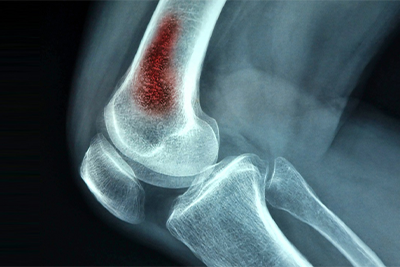

— Остеомиелит — кўмикнинг яллиғланиши билан кечадиган касаллик, — дейди мутахассис. — Уни содда қилиб суякнинг йирингли шамоллаши, деб ҳам атаса бўлади. Ушбу хасталик кўпинча одам скелети ғовак суякларининг бўғимга яқин жойида учрайди. Бунга йиринг ҳосил қилувчи микроблар, масалан, стафилококк, стрептококк сабаб бўлади.

Остеомиелит оқибатида йирингли артрит ривожланиши, суяк синиши, сепсис пайдо бўлиши ҳам амалиётда кузатилади.

Жумладан, остеомиелитга учраган найсимон суякларда паталогик синиш, суяк тўқимасининг чириши, ўсишдан тўхташи каби ҳолатлар шаклланиши мумкин.